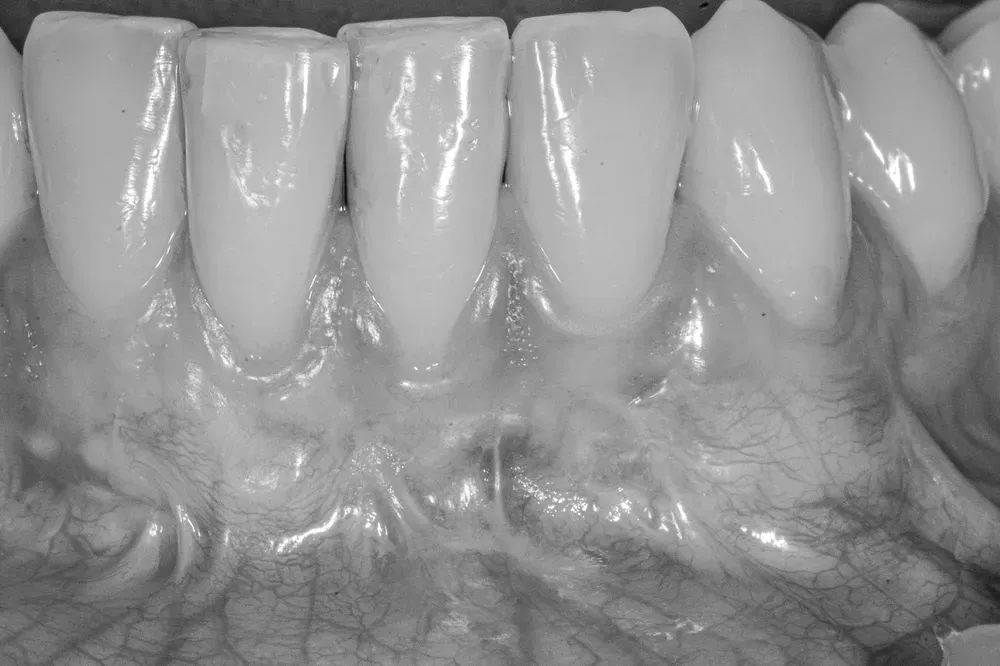

Immagine ravvicinata di denti con evidenti recessioni gengivali, mostrando la radice esposta e la mancanza di gengiva protettiva sulle superfici dentali.

Il caso di Marika prima dell’intervento